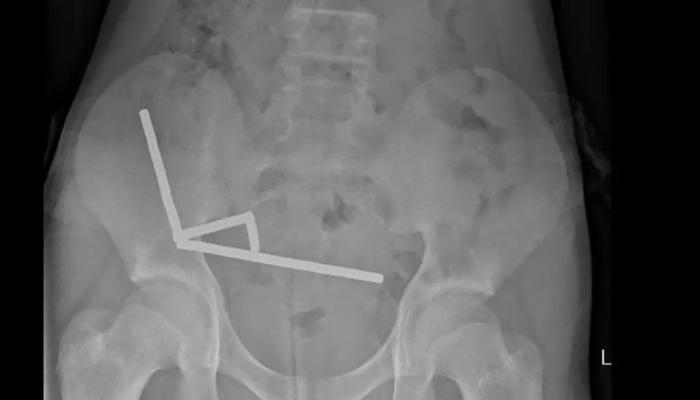

নিউজিল্যান্ডের ১৩ বছর বয়সী এক কিশোরের অন্ত্র থেকে প্রায় ১০০টি শক্তিশালী চুম্বক অপসারণ করেছেন সার্জনরা। অনলাইনে জনপ্রিয় মার্কেটপ্লেস টেমু থেকে কেনা এই উচ্চক্ষমতার চুম্বকগুলো গিলে ফেলেছিল কিশোরটি। চার দিন ধরে পেটে তীব্র ব্যথা অনুভব করার পর দেশটির উত্তর দ্বীপের তৌরাঙ্গা হাসপাতালে ভর্তি করা হয় তাকে। পরে এক্সরে স্ক্যানে দেখা যায়, চুম্বকগুলো তার অন্ত্রের ভেতর চারটি সরলরেখায় আটকে রয়েছে। নিউজিল্যান্ড মেডিকেল জার্নালে প্রকাশিত হাসপাতালের চিকিৎসকদের প্রতিবেদনে বলা হয়েছে, কিশোরটি প্রায় এক সপ্তাহ আগে ৮০ থেকে ১০০টি ৫২ মিমি মাপের নিওডিয়ামিয়াম চুম্বক গিলে ফেলেছিল। এসব চুম্বক ২০১৩ সাল থেকেই নিউজিল্যান্ডে নিষিদ্ধ। চিকিৎসকেরা জানিয়েছেন, চৌম্বকীয় আকর্ষণের কারণে অন্ত্রের বিভিন্ন অংশ একে অপরের সঙ্গে আটকে গিয়ে টিস্যু নষ্ট (নেক্রোসিস) হয়। এতে ক্ষুদ্রান্ত্র ও বৃহদান্ত্রের চারটি অংশ ক্ষতিগ্রস্ত হয়। অস্ত্রোপচারে মৃত টিস্যু অপসারণের পর কিশোরটি আট দিন চিকিৎসা শেষে বাড়ি ফিরে যায়। প্রতিবেদনের চিকিৎসকরা বলেছেন, এই ঘটনা শুধু চুম্বক গেলার বিপদ নয়, অনলাইন মার্কেটপ্লেস থেকে শিশুদের জন্য বিপজ্জনক পণ্য বিক্রির ঝুঁকিও তুলে ধরে। চিকিৎসকদের মতে, এমন অস্ত্রোপচারের পর অন্ত্রের বাধা, হার্নিয়া বা দীর্ঘস্থায়ী ব্যথার মতো জটিলতা পরবর্তী জীবনে দেখা দিতে পারে। এ ঘটনার পর অনলাইন মার্কেটপ্লেস টেমু এক বিবৃতিতে জানায়, তারা অভ্যন্তরীণ তদন্ত শুরু করেছে এবং বিষয়টি সম্পর্কে আরও তথ্য জানতে নিউজিল্যান্ড মেডিকেল জার্নালের লেখকদের সঙ্গে যোগাযোগ করেছে। টেমুর মুখপাত্র বলেন, ‘আমরা নিশ্চিত হতে পারিনি যে চুম্বকগুলো আমাদের প্ল্যাটফর্ম থেকেই কেনা হয়েছিল কিনা। তবে আমরা প্রাসঙ্গিক পণ্যগুলোর তালিকা পর্যালোচনা করছি, যেন স্থানীয় নিরাপত্তা পূর্ণ মানদণ্ড মেনে চলা হয়।’ চীনা মালিকানাধীন এই ই-কমার্স প্রতিষ্ঠান ইউরোপীয় ইউনিয়নসহ বিভিন্ন বাজারে নিষিদ্ধ বা ঝুঁকিপূর্ণ পণ্য বিক্রির অভিযোগে সমালোচনার মুখে রয়েছে। সূত্র/ দ্য গার্ডিয়ান